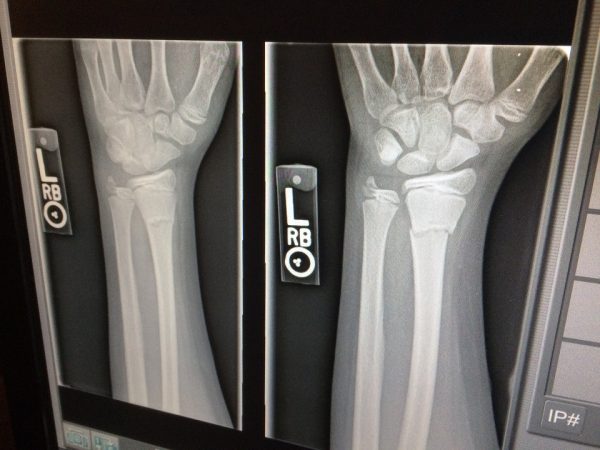

Fumar provoca que tus huesos disminuyan su densidad mineral. Por consiguiente, si tienes los huesos «más finos y débiles» el problema de sufrir roturas aumenta considerablemente. Si dejas de fumar las sustancias tóxicas que hacen que las células no regeneren los huesos se detienen y estas vuelven a actuar con normalidad.

Cuando tienes una fractura de un hueso los problemas aumentan por culpa de fumar. Está demostrado que los fumadores tienen casi el triple de probabilidades de que se les rompa un hueso de los largos como son la tibia o el fémur. Y lo que es peor, el proceso de recuperación es más lento.

Fumar hace que la rehabilitación y recuperación de una fractura sea mucho más lenta hasta en siete semanas más si eres fumador. Además, tienen el riesgo añadido de la infección que ya te he comentado, ya que el fumar hace que los microorganismos se reproduzcan con más facilidad.